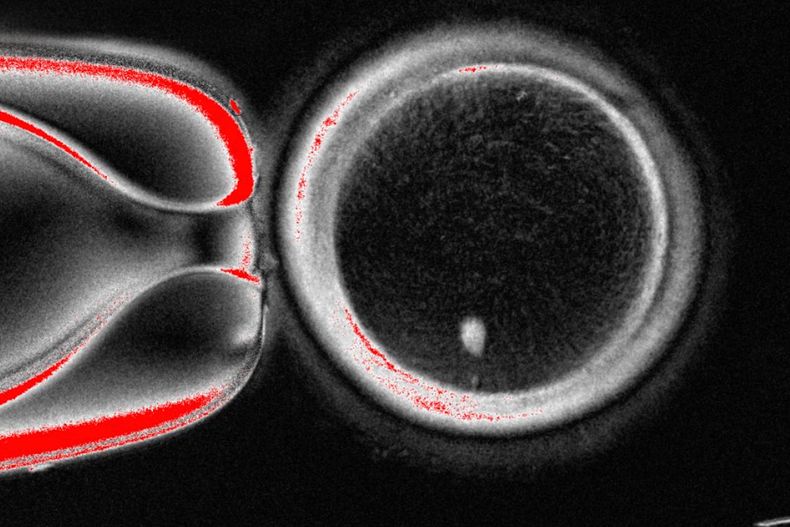

El equipo de OHSU extrajo el núcleo de una célula de óvulo humano y lo reemplazó con el núcleo de una célula de piel humana. Pero una célula de piel contiene dos conjuntos de cromosomas, y se supone que los óvulos y los espermatozoides deben contener solo un conjunto que se combine durante la fertilización. Por lo tanto, los investigadores indujeron a las células similares a óvulos a descartar cromosomas adicionales, inyectaron espermatozoides donados y activaron el desarrollo post-fertilización.

Aproximadamente el 9% duró seis días en platos de laboratorio, alcanzando la etapa de blastocisto del desarrollo temprano del embrión, antes de que se detuviera el experimento.

El problema principal: Los cromosomas eran anormales de varias maneras.

"Desarrollamos una nueva división celular que puede reducir el número de cromosomas", declaró Shoukhrat Mitalipov, autor principal del estudio y director de terapia génica y celular embrionaria de OHSU.